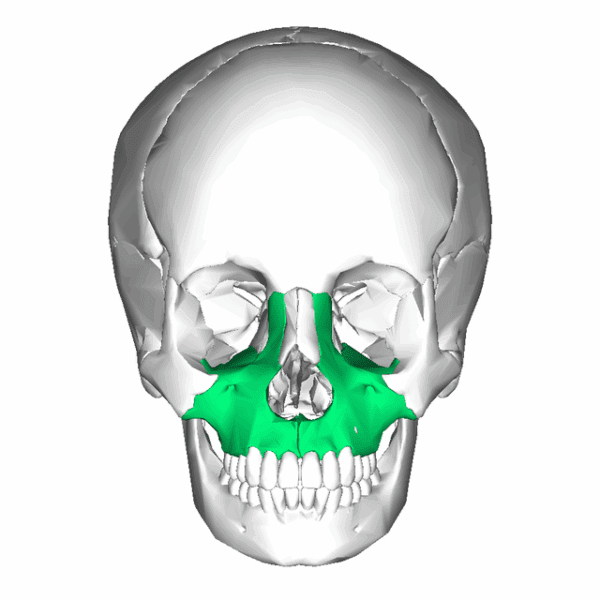

Habitual contact between the tongue and palate guides the growth and development of the craniofacial system. This contact provides a mechanical and cellular stimulus promoting bone growth (Singh et al, 2009). The gentle pressure of the tongue against the maxillary floor encourages forward, upward and outward expansion of the maxilla. Without this stimulus, the maxilla may remain narrow and elongated, setting the stage for restricted airways and altered facial development.

When the maxilla develops inadequately in width or forward projection, the nasal floor becomes restricted, potentially limiting airflow. This may lead to deviated septums, enlarged turbinates or adenoids and turbulent airflow. As nasal breathing becomes more difficult, mouth breathing often takes over, reinforcing dysfunctional postural and craniofacial patterns.

A lack of anterior or lateral maxillary growth reduces dental arch space, leading to crowding and potential Class II or III malocclusions. As previously discussed, these malocclusions are closely tied to postural imbalances.